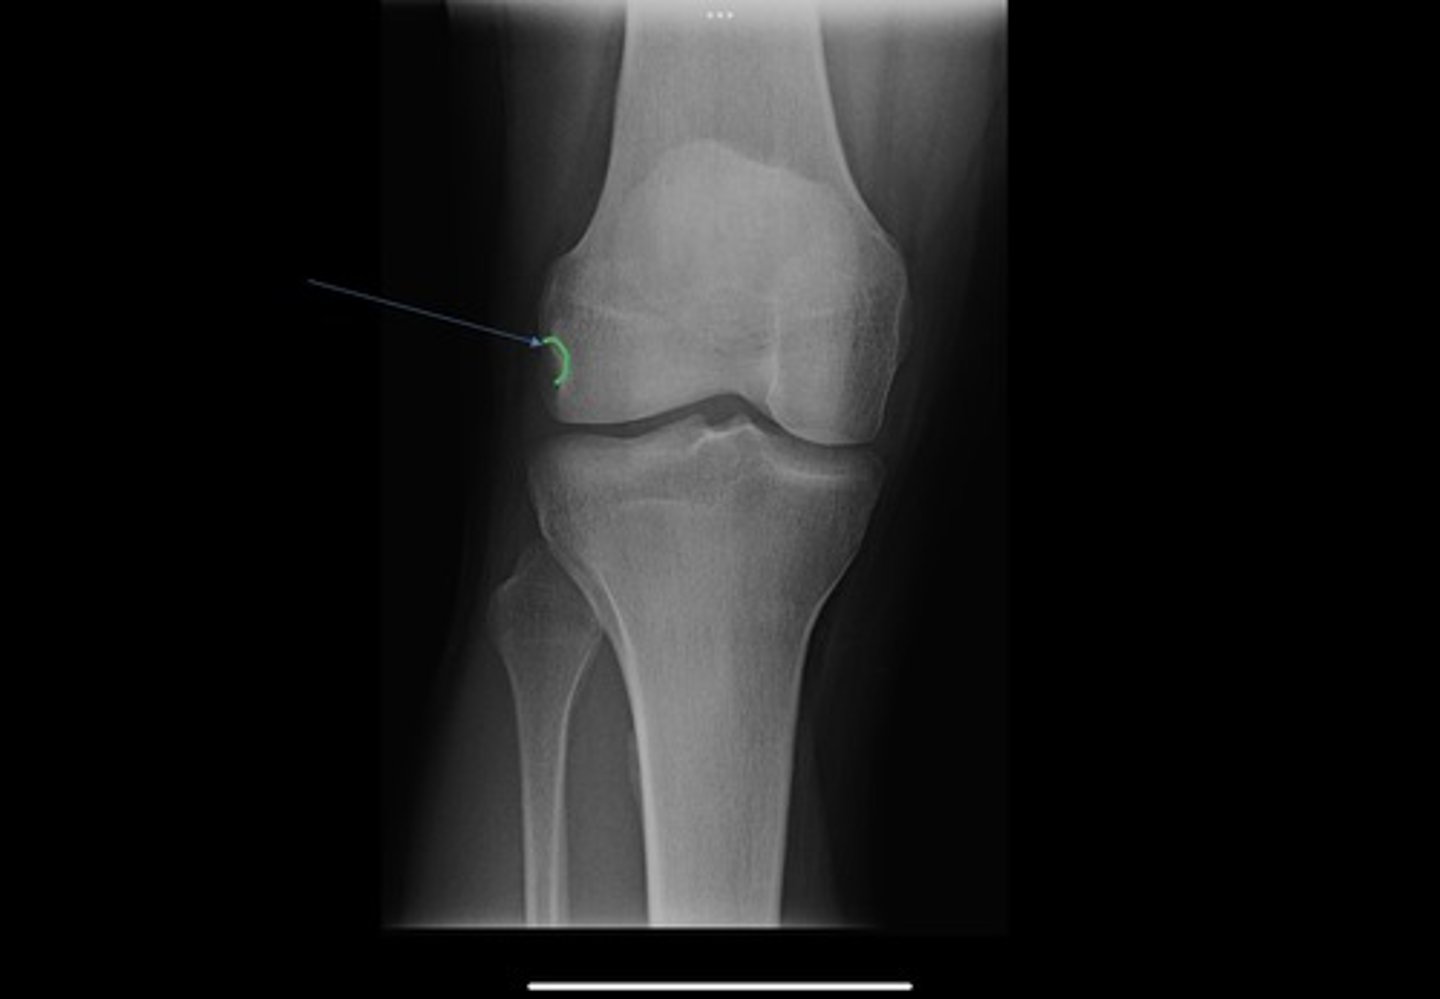

fibular head

fabella

ludloff spot